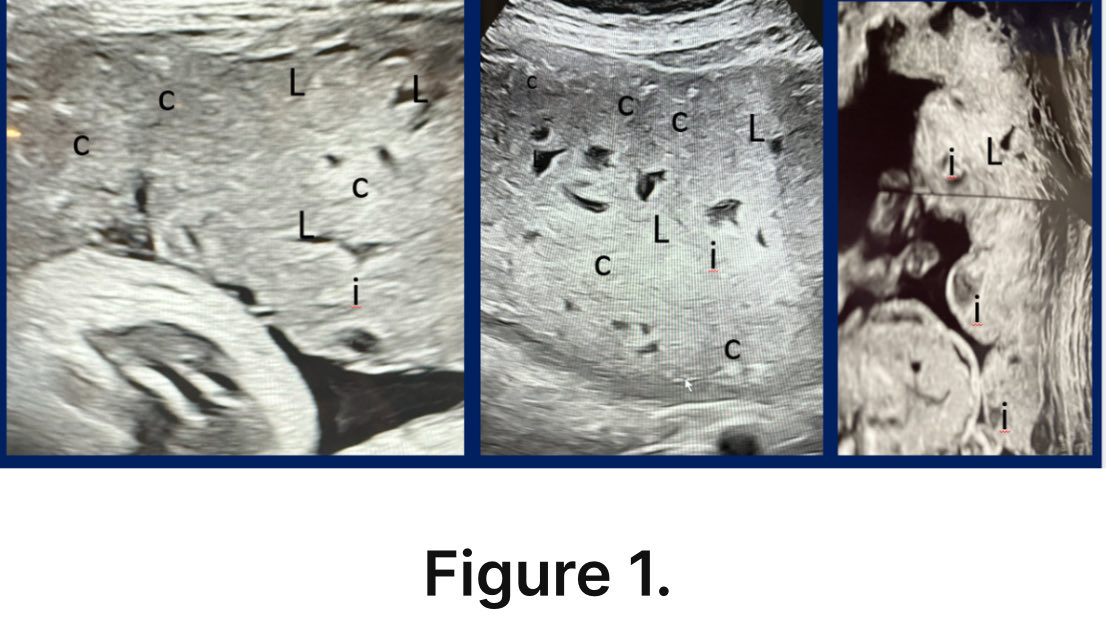

Since the onset of the COVID-19 Vaccinations I can confirm that I have witnessed significant increases in placental abnormalities including infarctions, lacunae, and calcifications.

These findings have been associated with fetal growth restriction, abruption, oligohydramnios and many other pregnancy complications.

L - Lacunae; i - Infarct;

L - Lake; C - Calcifications Image